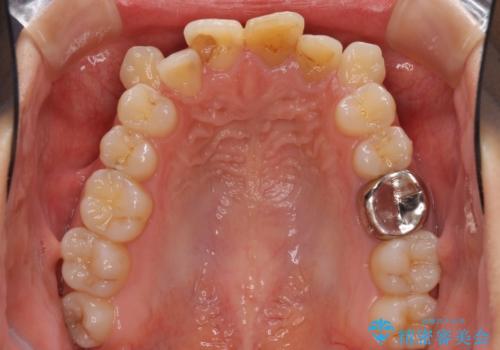

八重歯の抜歯矯正 費用を抑えた矯正装置

- 上の八重歯を気にして来院された患者様です。

受け口傾向にあるため、上顎前歯の叢生解消とともに下顎前歯を後方へ移動させることを目的とし、上下左右の第一小臼歯4歯を抜歯することとしました。